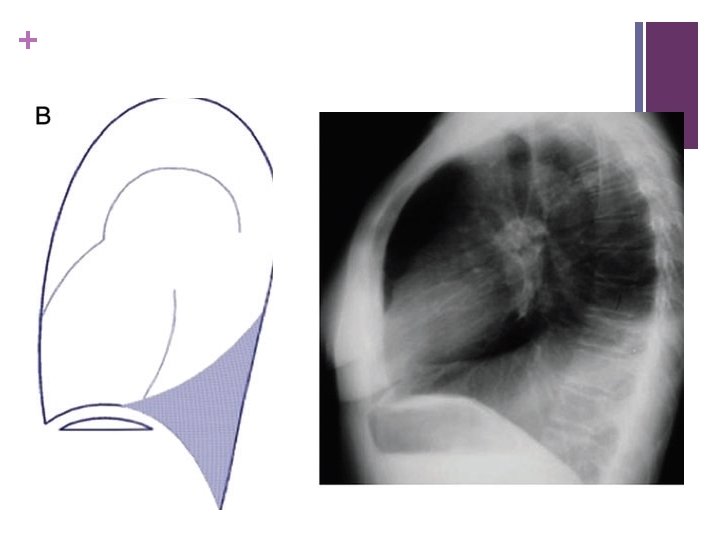

+ RLL collapse – obliteration Rt hemidiaphragm